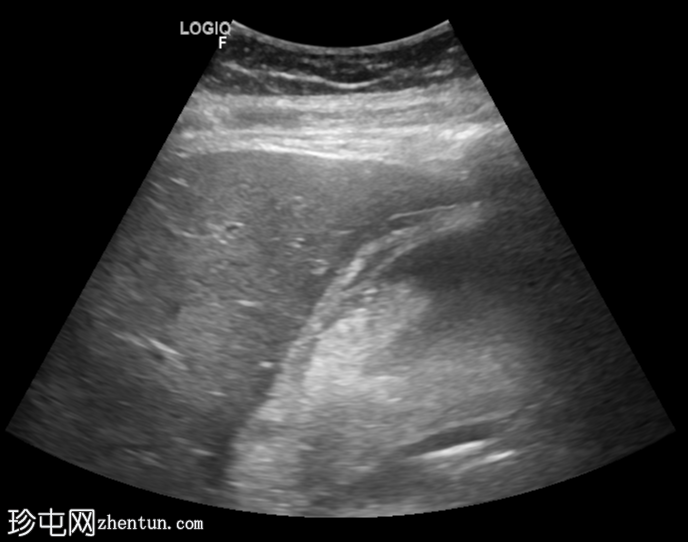

横切面

胆囊扩张,充满回声不均的异质性高回声物质(高回声、等回声、低回声),并可见漂浮回声。

可见胆囊周围水肿,胆囊壁不对称增厚,呈局灶性断裂,胆囊壁内可见强回声灶和强回声线(可能为气体腔)。

总体表现提示复杂性胆囊炎(坏疽性)。